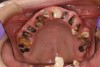

When smoked, methamphetamine produces highly toxic and corrosive fumes of lithium, muriatic, and sulfuric acids that can destroy enamel rapidly. With continued use, methamphetamine can produce severe, rampant caries, similar to early childhood caries. Patients have reported noticing changes in the appearance of tooth structure in as little as 3 months of use. The affected surfaces are the buccal and labial smooth surfaces, as well as the interproximal surfaces (Figure 1 through Figure 3). Because in the general population the vast majority of decay is found in the posterior molars, when someone presents with rampant anterior lesions it should be a red flag for methamphetamine use.5

Figure 2  DEVASTATING EFFECTS When smoked, methamphetamine produces highly toxic and corrosive fumes of lithium, muriatic, and sulfuric acids that can destroy enamel rapidly. With continued use, methamphetamine can produce severe, rampant caries. When someone presents with rampant anterior lesions it should be a red flag for methamphetamine use.

Figure 2